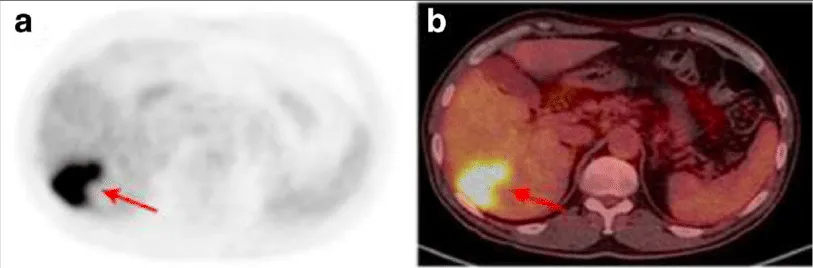

ПЭТ-изображение (слева) и ПЭТ/КТ-изображение (справа), полученные с использованием

ПЭТ-изображение (слева) и ПЭТ/КТ-изображение (справа), полученные с использованием 18F-фтордезоксиглюкозы // Tulin P., Dolgushin M. et al.